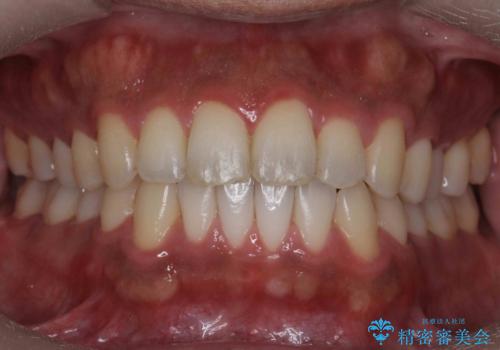

[ 前歯のねじれ・がたつき ] マウスピース矯正

![[ 前歯のねじれ・がたつき ] マウスピース矯正の症例 治療前](https://seimitsushinbi.jp/wp/wp-content/uploads/2024/02/4007c6479f6bce11863dcdd32ed5e39b-500x350.jpg?v=1708502552)

![[ 前歯のねじれ・がたつき ] マウスピース矯正の症例 治療後](https://seimitsushinbi.jp/wp/wp-content/uploads/2024/02/e7a01485e4f4dd0da04705fde4cc34cc-500x350.jpg?v=1708502585)